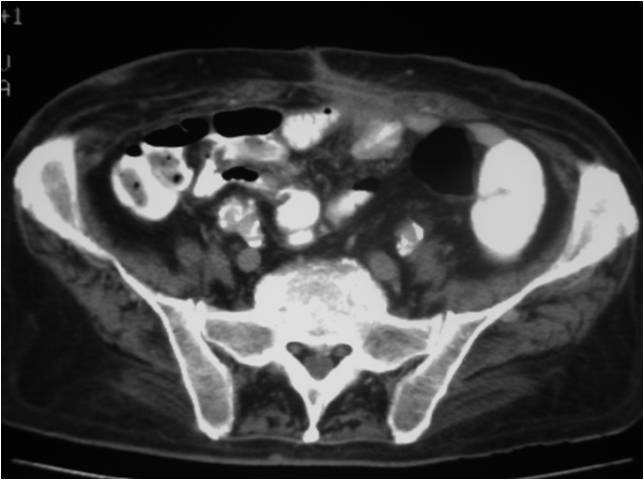

- Abscess post left hemicolectomy

- Successful placement and drainage